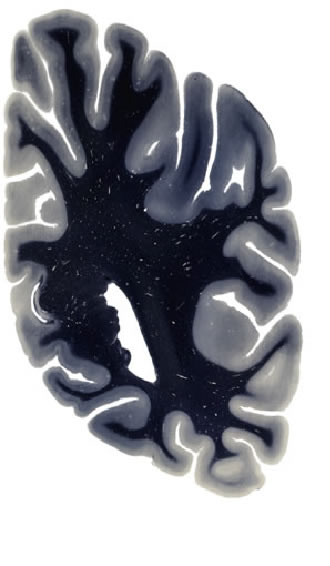

Hi-Resolution Sections · Cells (Nissl Staining) · Virtual Microscopy

Frontal sections (Nissl) from the Atlas Brain:

Slice ID:

r4-0421

Plate NR:

54

Position:

48,1 mm